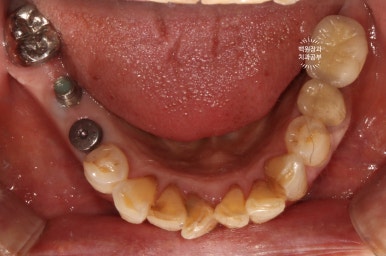

좌측은 위턱 사진, 오른쪽은 아래턱 구강내 사진입니다.

아주 어렵지 않게 두 치아가 부러져 있다는 것을 확인할 수 있죠.

보시면 이가 없던 자리에 임플란트 두개가 생겨 있는 것을 보실 수 있습니다.

발치 동시 임플란트의 또 다른 특징으로, 대부분 임플란트 2차수술을 하지 않습니다.

왜냐~ 이를 뽑으면서 임플란트를 바로 심기 때문에, 잇몸이 비어있는 부분이 있잖아요? ㅎㅎ 그러니 당연히 뚜껑을 껴야한다구요!! 그래서 임플란트 수술이 모두 끝나버립니다.